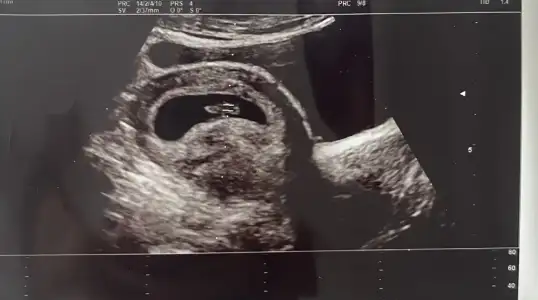

melegim can melegim can canımm bu bebiş vajınalde gecen haftaya gore diğer tarafta gozukuyo bu sefer kıza mı dondu acaba 😂😍

Demedi, bugün acile gitmiştim grip ve ateşli olduğum için orda kontrol amaçlı bebeğe baktırdım önce. Doktor da ultrason görüntüsüne yorum yapmadı benim de aklıma o geliyor